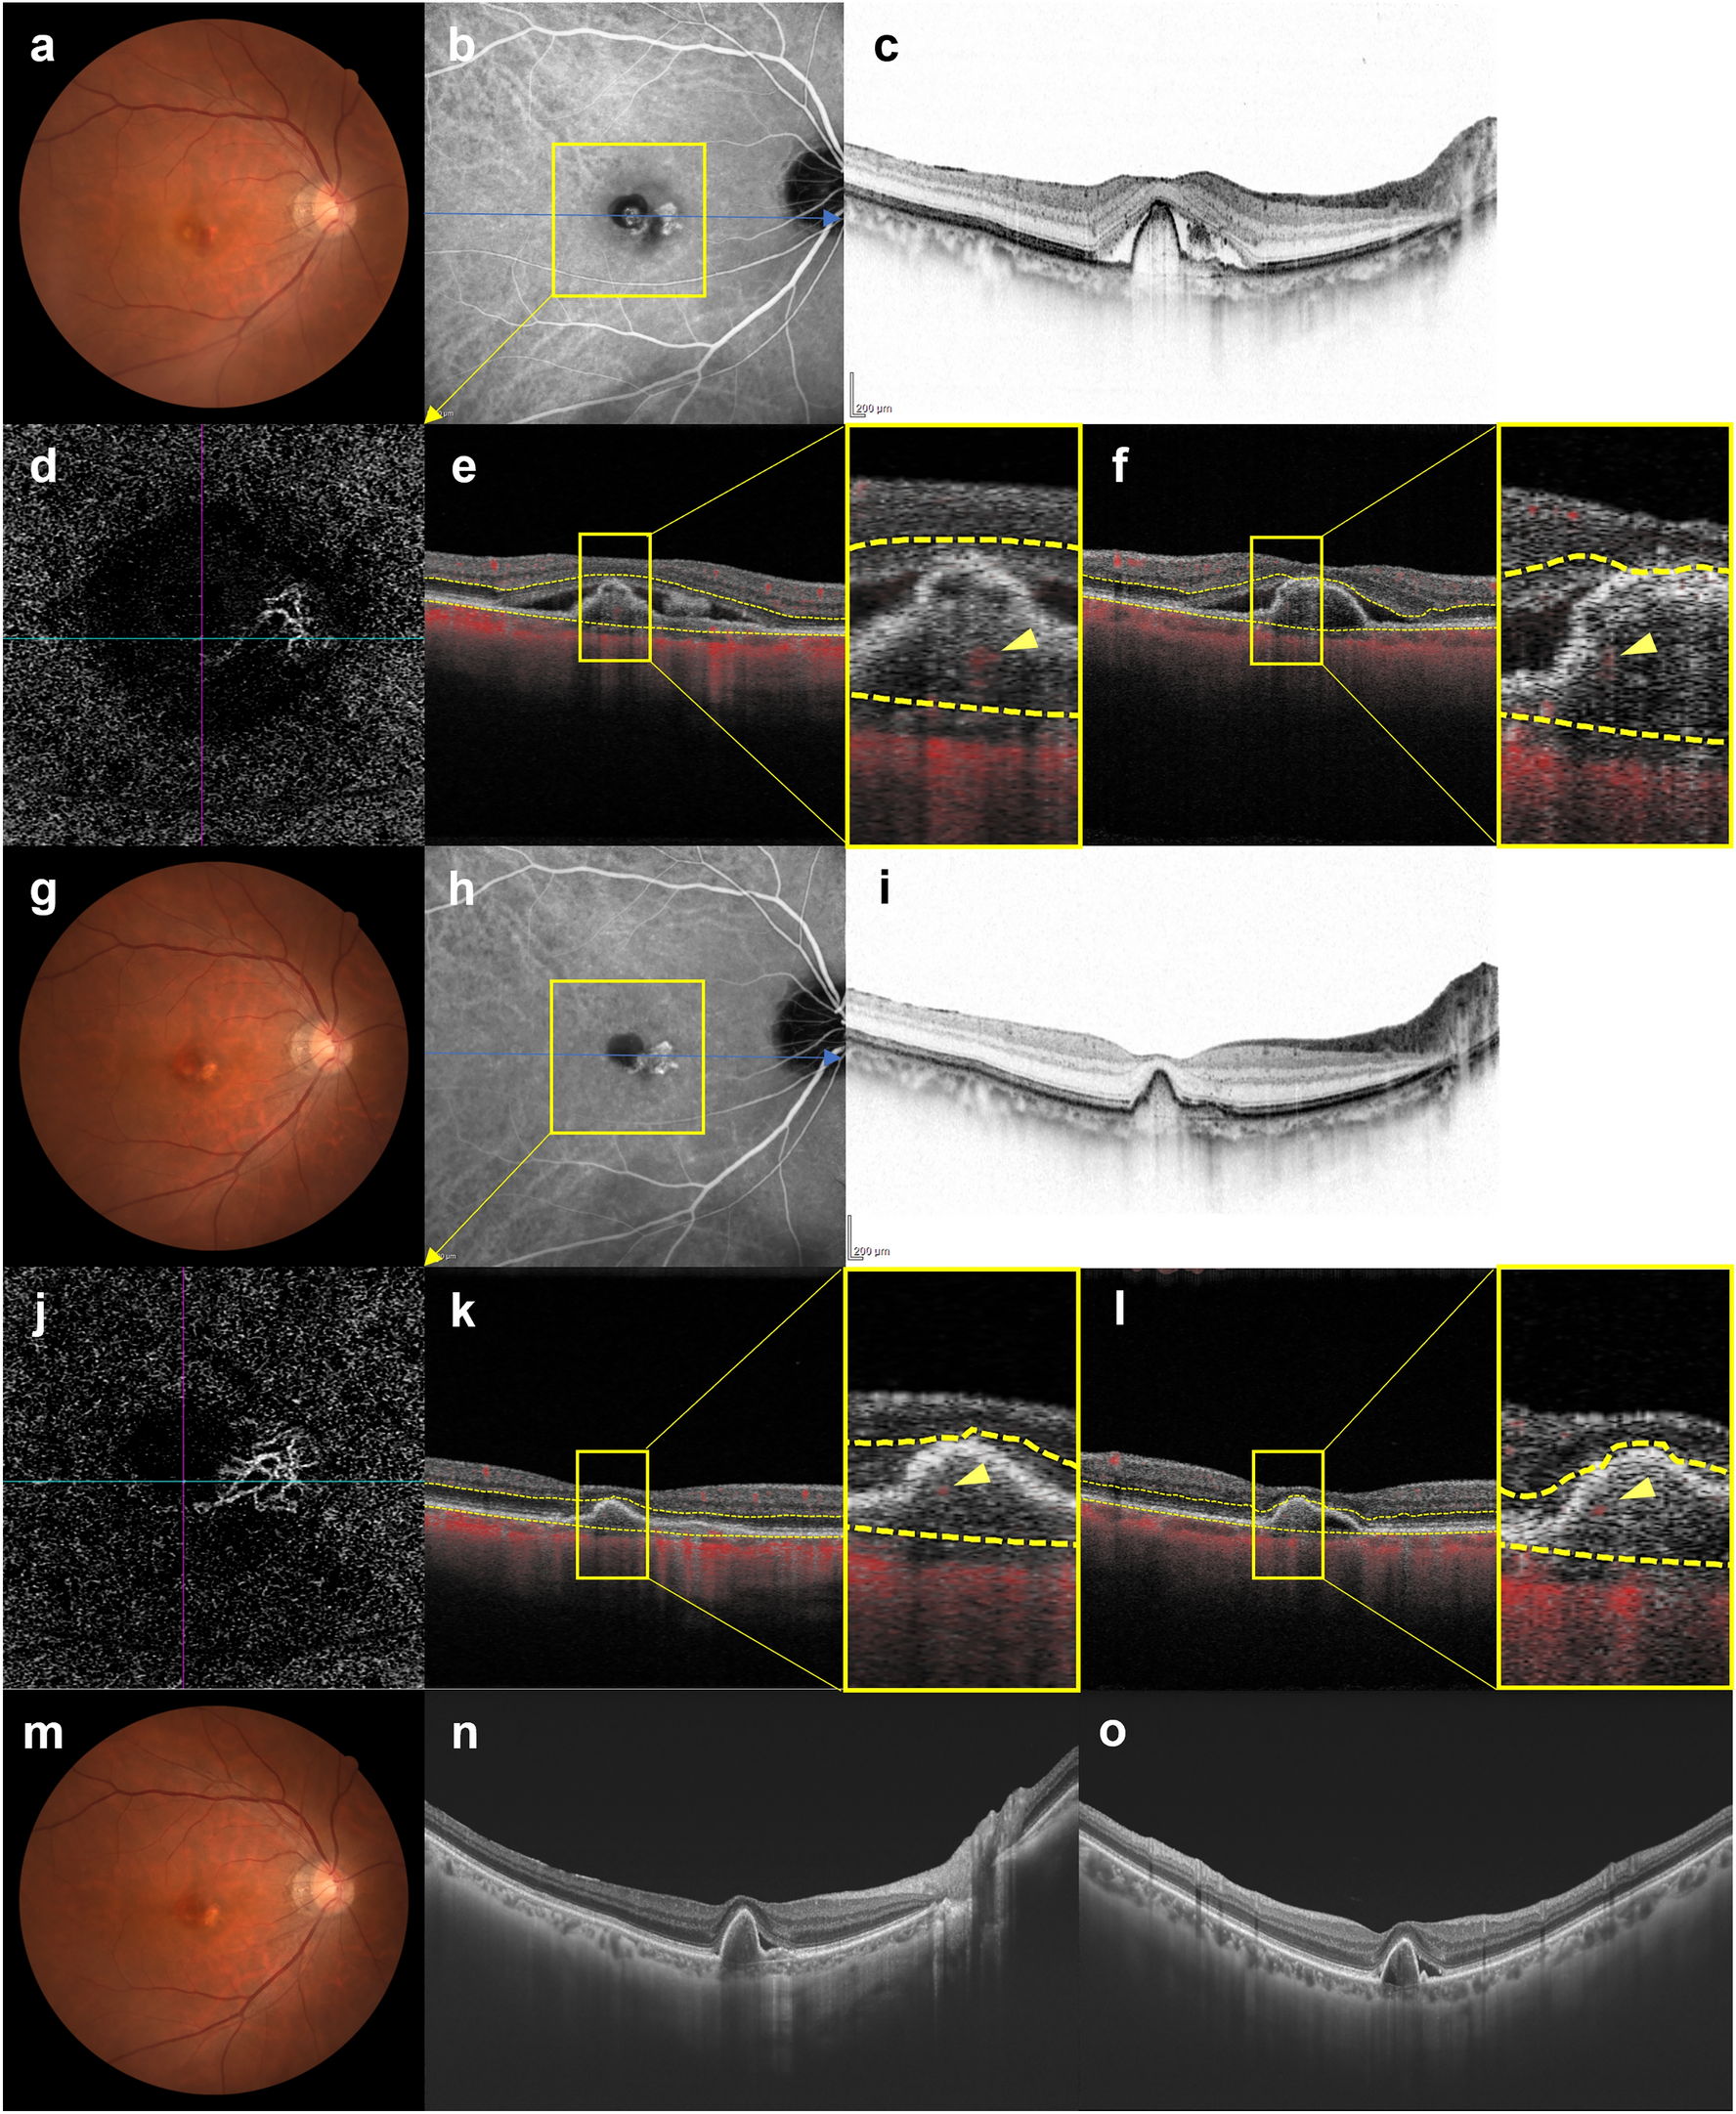

Figure 6

Images of the right eye of a 69-year-old man with polypoidal choroidal vasculopathy in the group showing persistence of blood flow signals within polypoidal lesions. (a–f) Baseline. Best corrected-visual acuity (BCVA) of the right eye is − 0.08 logarithm of the minimal angle of resolution (logMAR) units. (a) Color fundus photograph shows an orange-red lesion accompanied by subretinal hemorrhage. (b) Indocyanine green angiography (ICGA) shows a polypoidal lesion with a branching neovascular network (BVN). (c) Optical coherence tomography (OCT) B-scan image through the fovea shows a sharp-peaked and shallow irregular pigment epithelial detachment (PED) with serous retinal detachment (SRD). (d) Optical coherence tomography angiography (OCTA) en face image shows blood flow signals corresponding to the polypoidal lesion and the BVN. (e, f) OCTA B-scan images (e: horizontal, f: vertical) show blood flow signals within the PED corresponding to the polypoidal lesion (arrowheads). (g–l) 3 months after the initial treatment. BCVA of the right eye is − 0.08 logMAR units. (g) Color fundus photograph shows no subretinal hemorrhage. (h) ICGA shows complete regression of the polypoidal lesion. (i) OCT B-scan shows the sharp-peaked PED to be diminished without SRD. (j) OCTA en face image shows unclear blood flow signals within the polypoidal lesion. (k, l) OCTA B-scan images (k: horizontal, l: vertical) show blood flow signals within the PED corresponding to the polypoidal lesion (arrowheads). (m–o) 6 months after the initial treatment. BCVA of the right eye is − 0.08 logMAR units. (m) Color fundus photograph shows no subretinal hemorrhage. (n, o) OCT B-scan images through the fovea (n: horizontal, o: vertical) show SRD recurrence and an enlargement of the sharp-peaked PED. In total, 8 injections were required during the 1-year study period due to SRD recurrence.